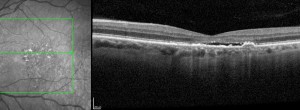

MANTRA: evaluación de la asociación entre la sensibilidad y el flujo retiniano en la DMAE